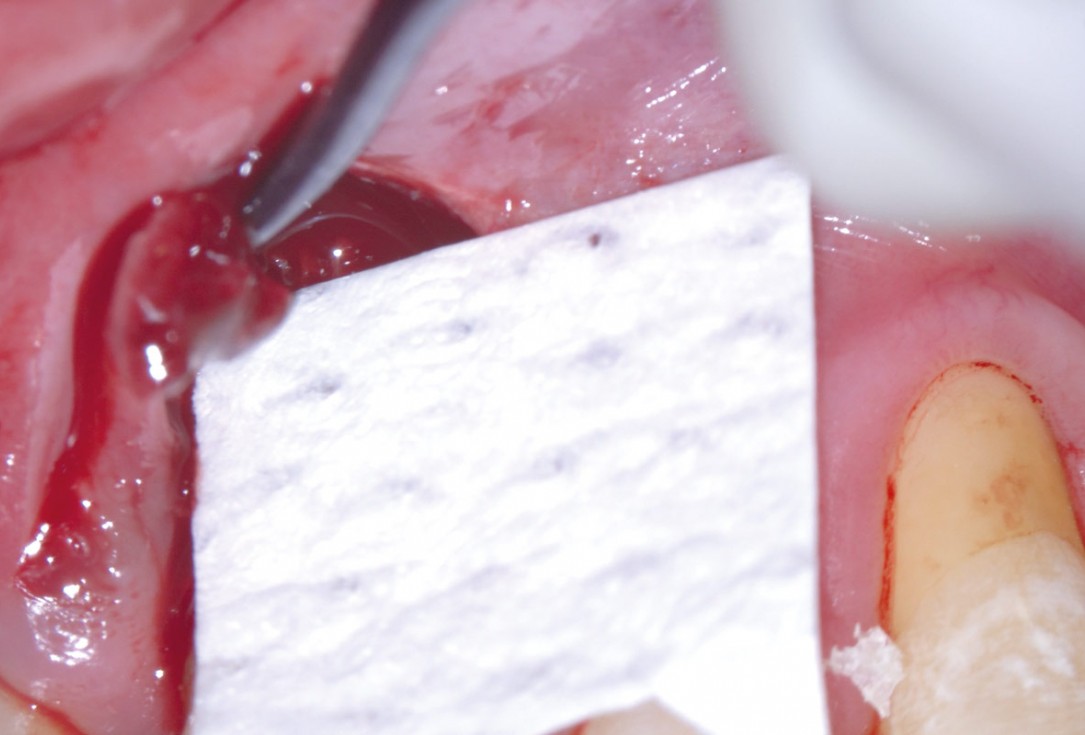

05/11 - Application of maxgraft® granules to fill the defectEntire papilla preservation technique (EPP) for the regenerative treatment of a severely compromised central incisor - Dr. S. Aslan